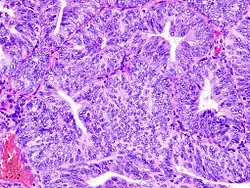

Histopathologic and cytopathologic images.

(A) proliferative endometrium (Left: HE × 400) and proliferative endometrial cells (Right: HE × 100)

(B) secretory endometrium (Left: HE × 10) and secretory endometrial cells (Right: HE × 10)

(C) atrophic endometrium (Left: HE × 10) and atrophic endometrial cells (Right: HE × 10)

(D) mixed endometrium (Left: HE × 10) and mixed endometrial cells (Right: HE × 10)

(E): endometrial atypical hyperplasia (Left: HE × 10) and endometrial atypical cells (Right: HE × 200)

(F) endometrial carcinoma (Left: HE × 400) and endometrial cancer cells (Right: HE × 400).